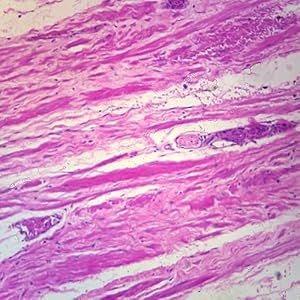

Human Mammary Gland Resting Microscope Slide